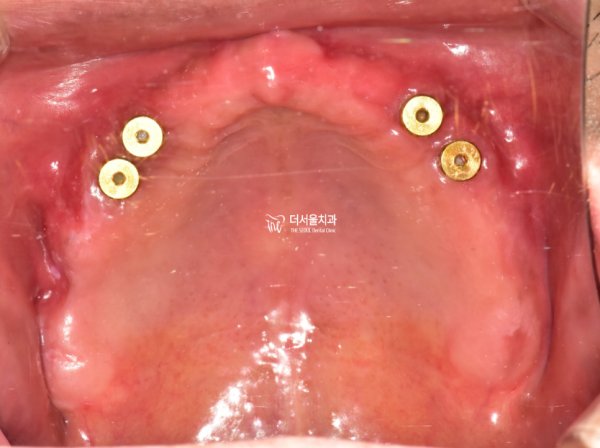

보철을 부착하기 전의 상악의 모습입니다.

바로 저 부분에 오버덴쳐가 강력하게 결합게되는 것 입니다.

이를 통해 기존의 틀니보다 단단한 저작력과 지지력을 가질 수 있습니다.

This is the image of the maxilla before attaching the prosthesis.

That's where the overdenture is strongly coupled.

This allows for stronger copyright and support than conventional dentures.